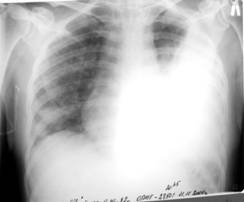

Науқас 32 жаста, кеуде жасушасы сол бөлігіндегі ауырсынуға шағымданды, дем алу қиындығымен демікпе көрсетілген. Кенеттен ауырған, жөтелдін әсерінен кеуде жасушасының сол жақ бөлігінде ауырсыну пайда болды, тездетіп демікпе үдей бастады. Объективті: ерін цианозы, кеуде жасушасының сол жақ жартысы үлкейгені соншама, тыныс алу актісінен қалып қояды, мойын тамырларының ісінуі белгіленді. Перкуссияда: сол жақта дыбыстын тимпаникалық түрі, перкуторлы сол жақ өкпенің төменгі шегі төмен түскен (аурудын ауыр жағдайына байланысты төменгі шетінің қозғалғыштығы анықталмаған). Аускультацияда везикулярлық тыныс алу кенеттен босаңсыңғаны байқалады. Кеуде қуысы шолымды рентгенографиясы таѓайындалды.

Нақты клиникорентгенологиялық сурет қандай патологияѓа үзінді:

A) Пневмоторакс

{Дұрыс жауабы} = A